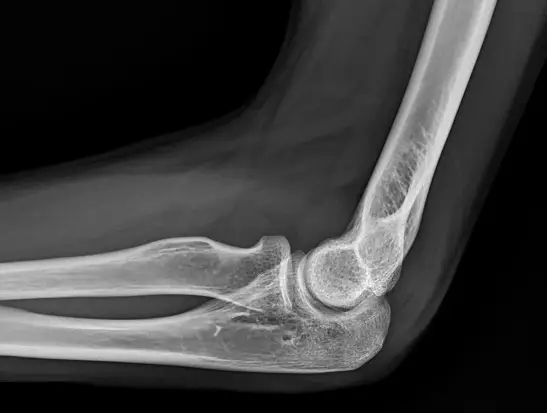

病人跌倒後被送到急診室,左手肘劇烈疼痛且無法活動。他的左手肘 X 光片側面照的影像如圖所示,下列敘述何者最恰當?

側位肘關節X光上「fat pad sign」(脂肪墊徵象)代表關節腔內積液,常見於急性創傷後的肘關節積血或積液,可間接提示隱藏性(occult)骨折。

從側面照可見遠端 humerus 與 proximal radius、ulna 關節面無明顯骨折裂隙。正常時, anterior fat pad(前脂肪墊)雖可見但緊貼骨面、不呈抬升; posterior fat pad(後脂肪墊)則隱藏於 olecranon fossa,通常不見。本案例 anterior fat pad 有明顯「船帆狀」抬升(sail sign),且可見 posterior fat pad,代表肘關節內有液體(血或其他液體)使脂肪墊被推開,形成 joint effusion 的典型表現。

選項A “可明顯發現肱骨(humerus)骨折”

X光未見 humerus 遠端(髁部)或骨幹的皮質中斷、移位或碎骨,排除明顯骨折。 -

選項B “可明顯發現橈骨(radius)骨折”

radius 頭及頸部骨皮質完整,無裂隙或錯位,不符合橈骨骨折特徵。 -

選項C “生長板(growth plate)尚未癒合”

此患者X光骨化中心已融合,未見未癒合之生長板線。且題目並未交代未成年身分,影像亦符合成年骨骼特徵。 -

選項D “可明顯發